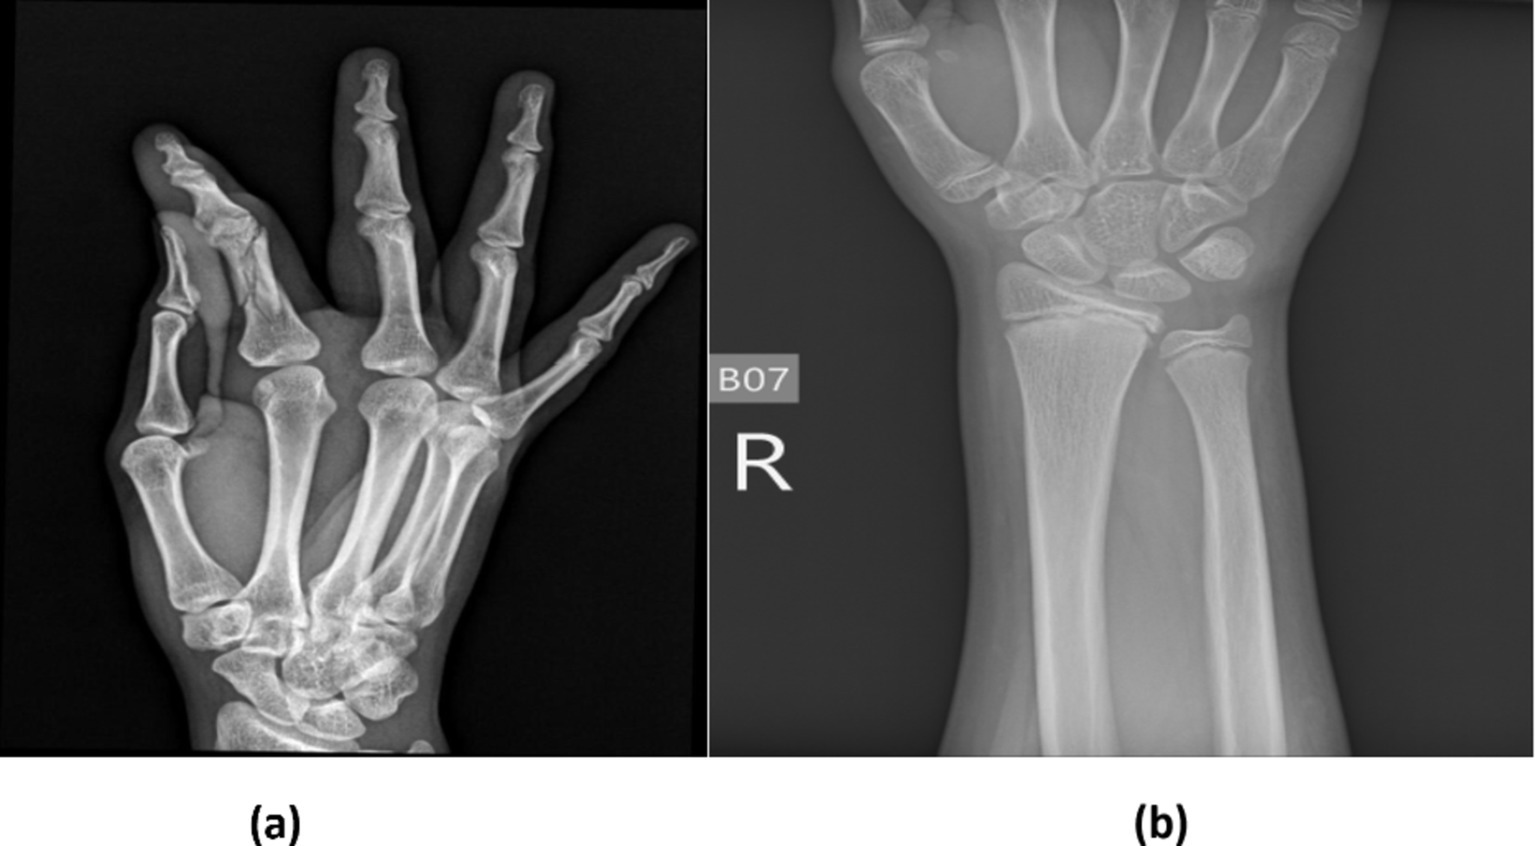

In recent years, machine learning (ML) and deep learning (DL) methods have gained prominence in real-time medical analysis (4, 5). Various deep convolutional neural network (CNN) models have demonstrated success across multiple applications (6, 7). Bone fractures, as common injuries, necessitate immediate diagnosis. Although medical imaging system was sue to detect fractures, these images can be time-consuming, prone to error, and dependent on the clinician’s expertise (8, 9). Artificial intelligence (AI) technologies offer the potential to automate diagnostic processes, improving the speed and accuracy of fracture detection (10–13).The research has been conducted on the application of AI to bone fracture identification (14, 15). The different types of bone fractures are illustrated in Figure 1.

Figure 1

Shows bone fracture samples from the dataset.